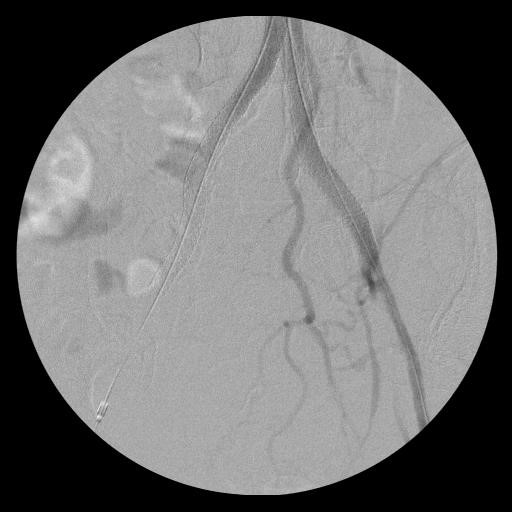

Субинтимальная реканализация